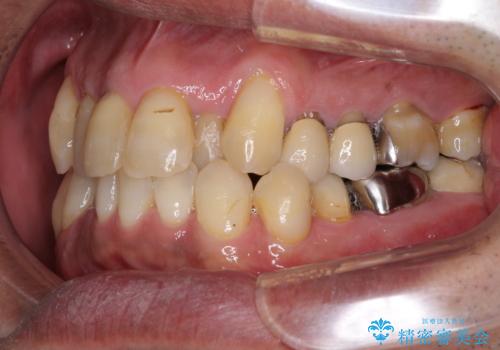

- 前歯がのデコボコや、奥歯に咬んだときに痛みがあるとのことで来院された患者様です。

全体的に問題が多く、全てをしっかりと治療したいとのことでした。

全体的に中等度の歯周病と診断されたため、歯周外科処置やインプラントによる咬合回復から進めて行き、矯正治療による歯列改善を行った後にオールセラミッククラウンにて補綴することとしました。